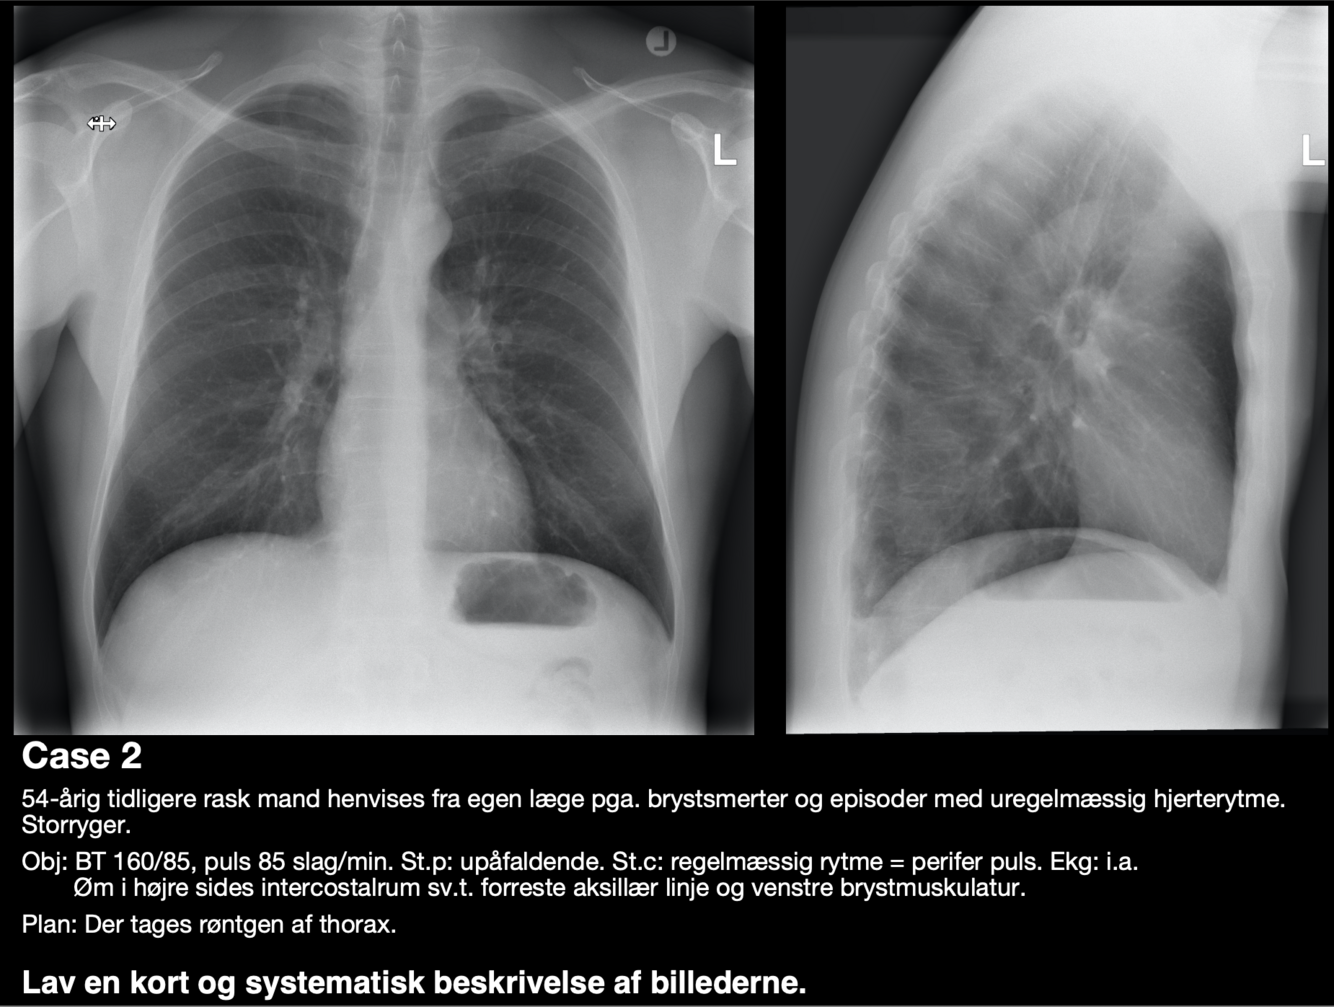

Q

Diagnose?

A

Centralt lokaliseret lungecancer (obs malign tumor i højre hilus)